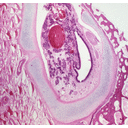

LarynxSheep.jpg